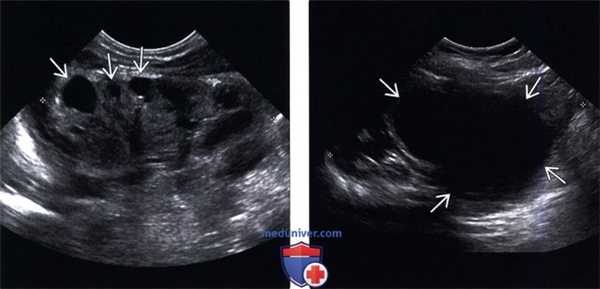

(Левый) На продольном УЗ срезе визуализируются диспластические кистозные изменения в верхнем полюсе почки, в результате обструкции, сопровождающейся потерей кортикомедуллярной дифференциации и истончением коркового вещества.

(Правый) На продольном УЗ срезе визуализируется значительное расширение лоханки нижнего отдела почки вследствие обструкции лоханочно-мочеточникового сегмента.

(Левый) На поперечном УЗ срезе визуализируется округлое тонкостенное анэхогенное образование в полости мочевого пузыря в сочетании с уретероцеле.

(Правый) На экстреторной цистоуретрограмме визуализируется симптом завянувшей лилии с контрастированием мочеточника и лоханки нижнего отдела почки и изменением нормальной оси вследствие обструкции верхней лоханки.